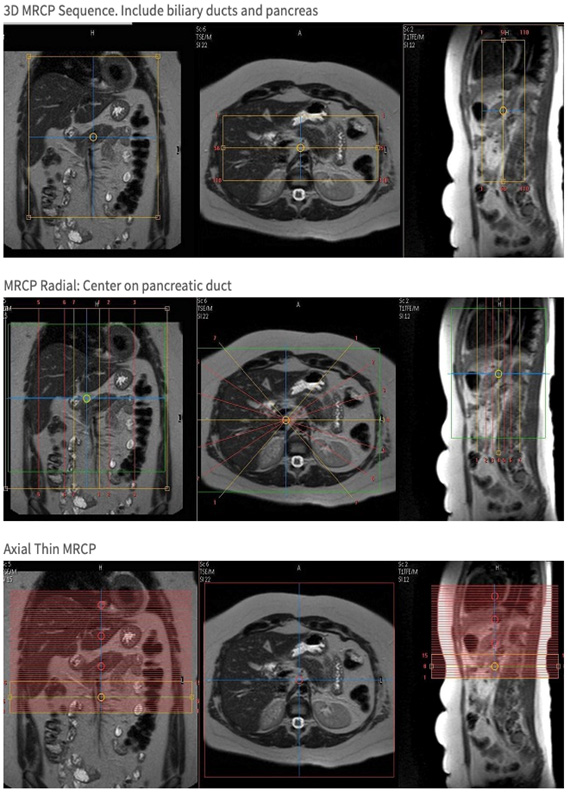

| Cor | T2 | 3D MRCP | 1.4mm | Yes | Bottom 2/3 of liver through bottom of pancreas | Please use navigator trigger & track. | |

| Cor | T2 | Radial MRCP | 40mm | Yes | Liver through bottom of kidneys | Please use navigator trigger & track. | |